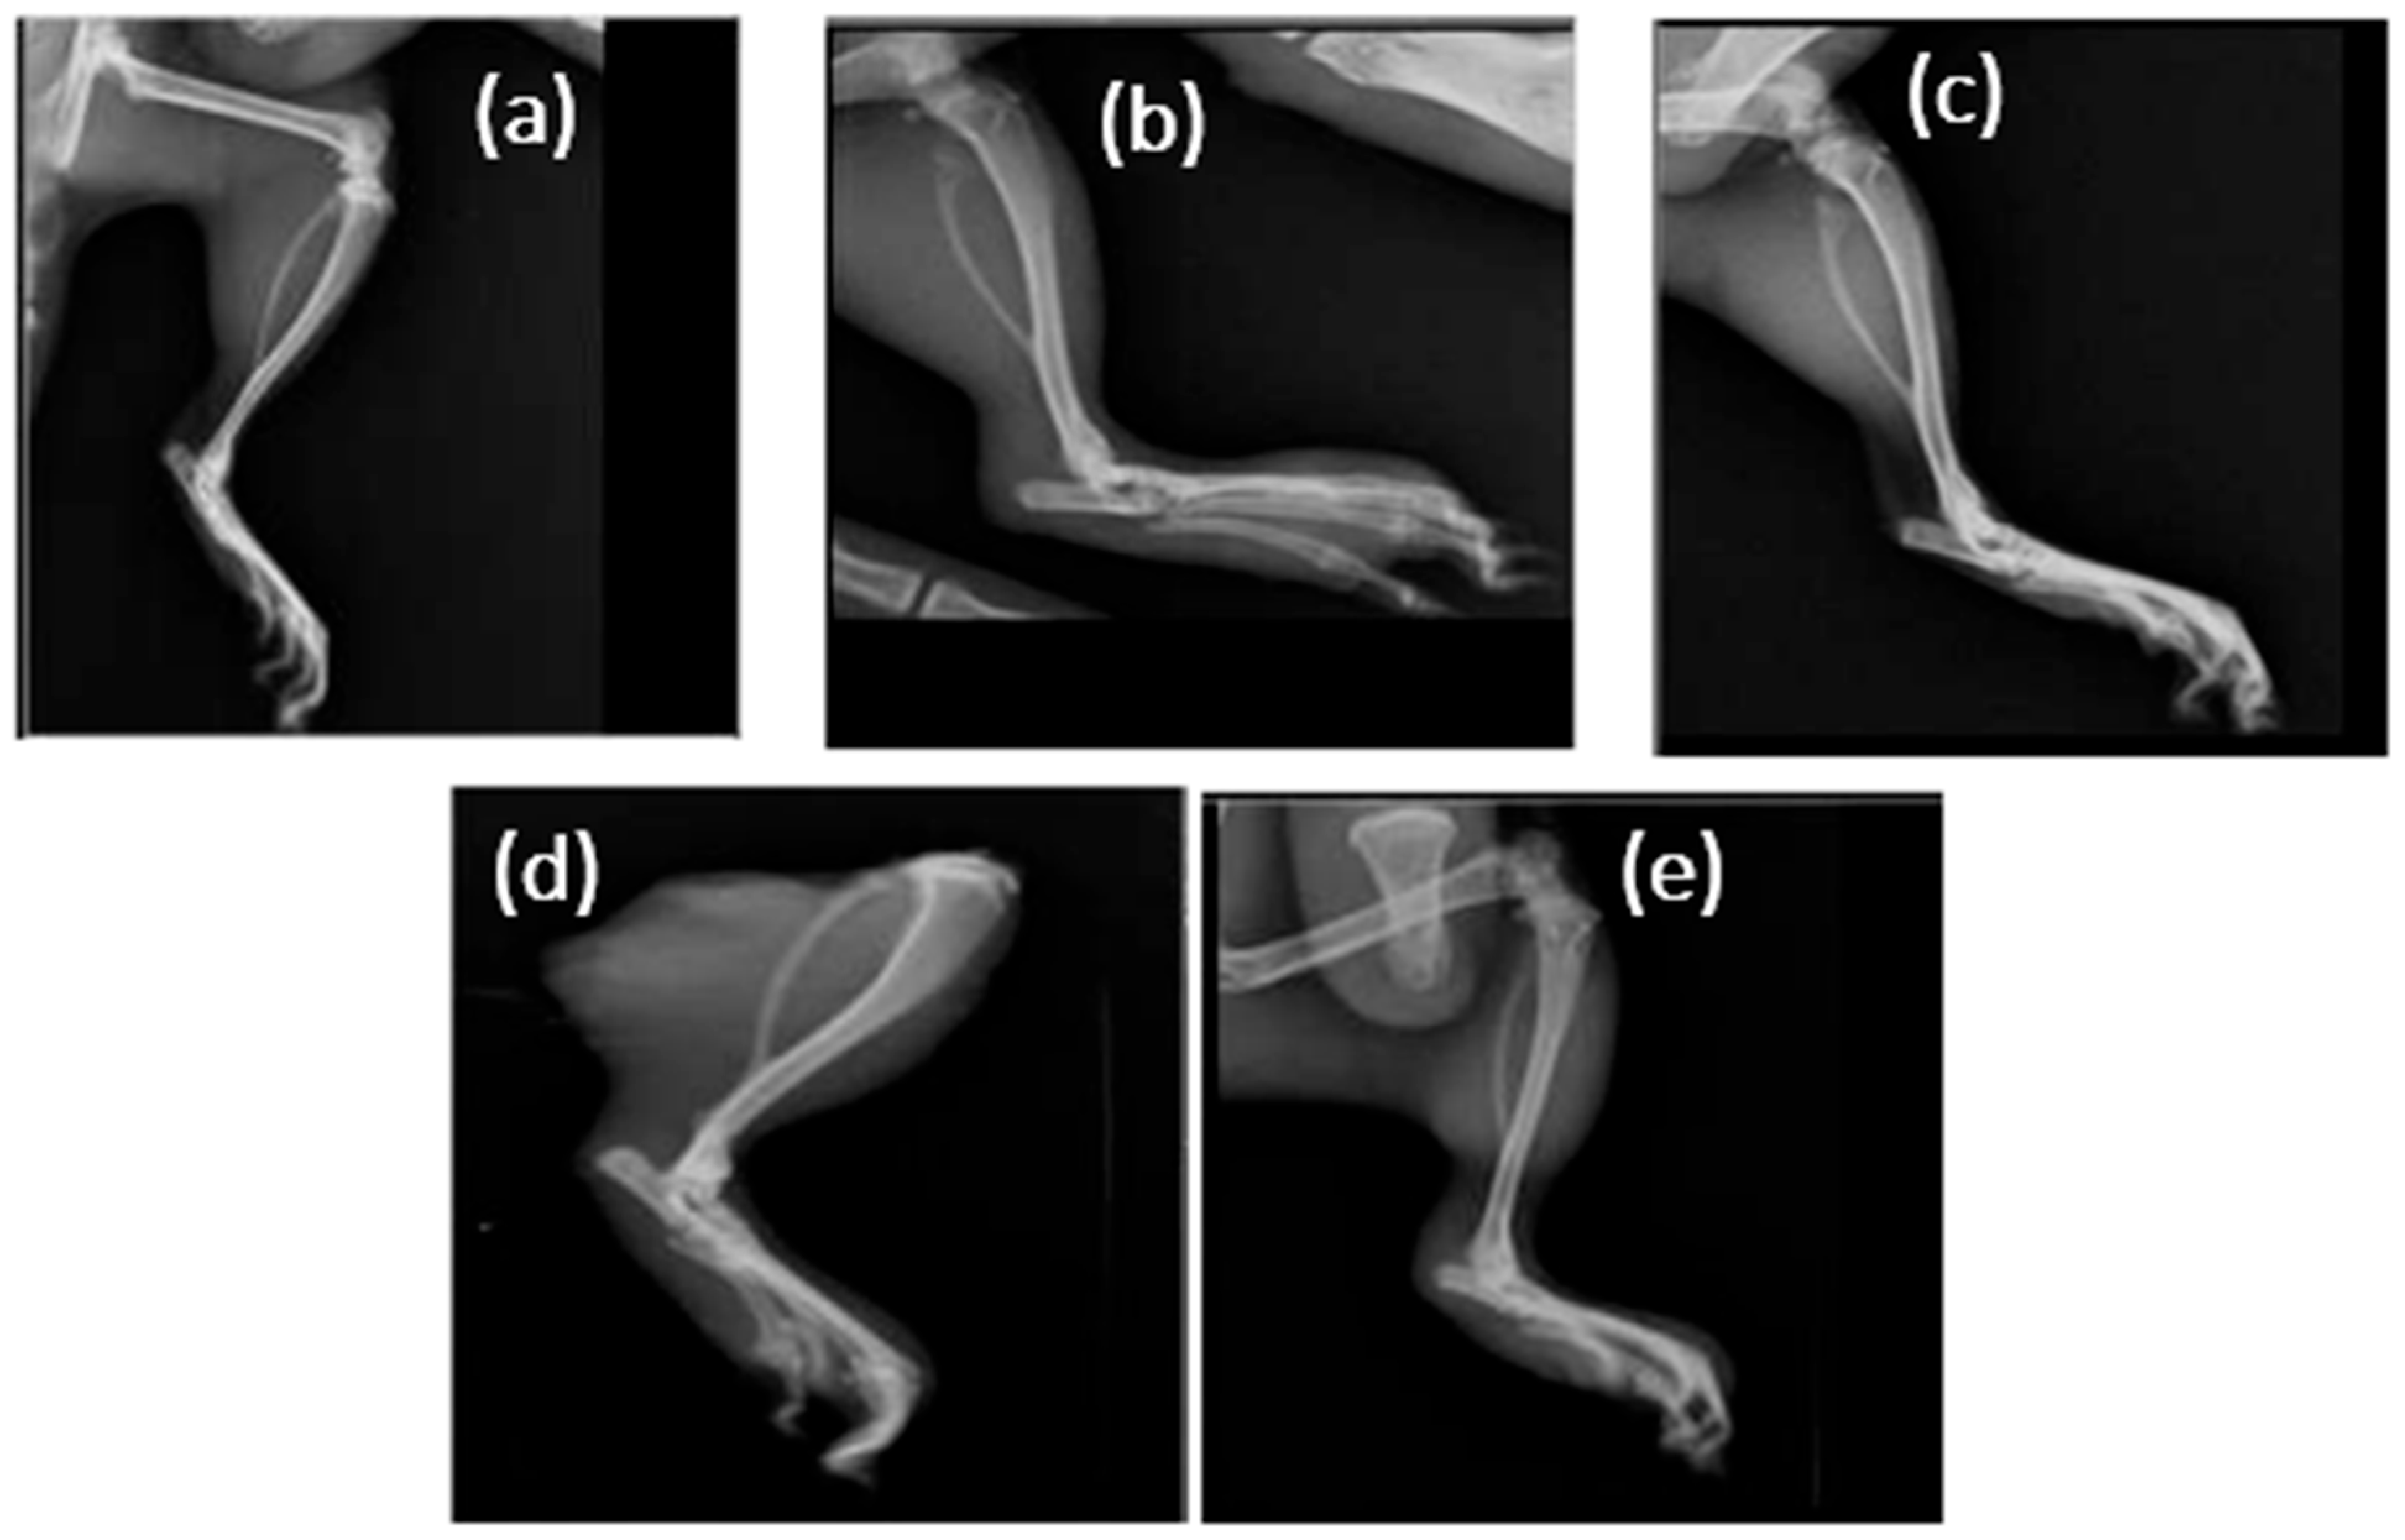

3.5. Radiographic Examinations